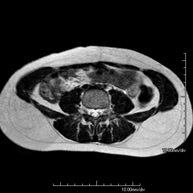

- RM Pelvis masculina

Prueba diagnóstica no invasiva que consiste en la obtención de imágenes de alta definición anatómica de la pelvis masculina mediante el empleo de un campo electromagnético y ondas de radio (con un emisor y un receptor). No utiliza radiación ionizante. No requiere de preparación previa. En algunas ocasiones requiere el empleo de contraste paramagnético (Gadolinio) para caracterizar las lesiones. Esta prueba permite valorar órganos como la vejiga urinaria, la unión entre los uréteres y la vejiga, la próstata, las vesículas seminales, la uretra, los huesos de la pelvis, etc.